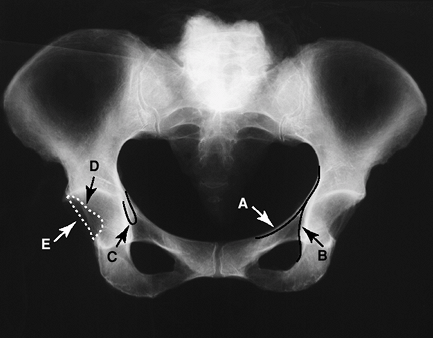

Figure 2-8 Radiographic landmarks of the pelvis. A, iliopectineal line; B, ilioischial line; C, acetabular teardrop; D, anterior acetabular rim; E, posterior acetabular rim.

Iliopectineal line: denotes anterior column

-

Ilioischial line: denotes posterior column

Teardrop: inferior margin of the medial acetabular border.

Anterior acetabular rim

Posterior acetabular rim

inferior border of the superior pubic ramus and the medial border of

the femoral neck. Helpful in evaluating the relationship of the femoral

head to the acetabulum. A break in the Shenton line indicates migration

of the femoral head.

center of the femoral head to the edge of the acetabulum. A second line

is drawn vertically to the center of the femoral head to form the

incident angle.

ischium to the medial border of ilium. Penetration medial to this line

indicates protrusion.